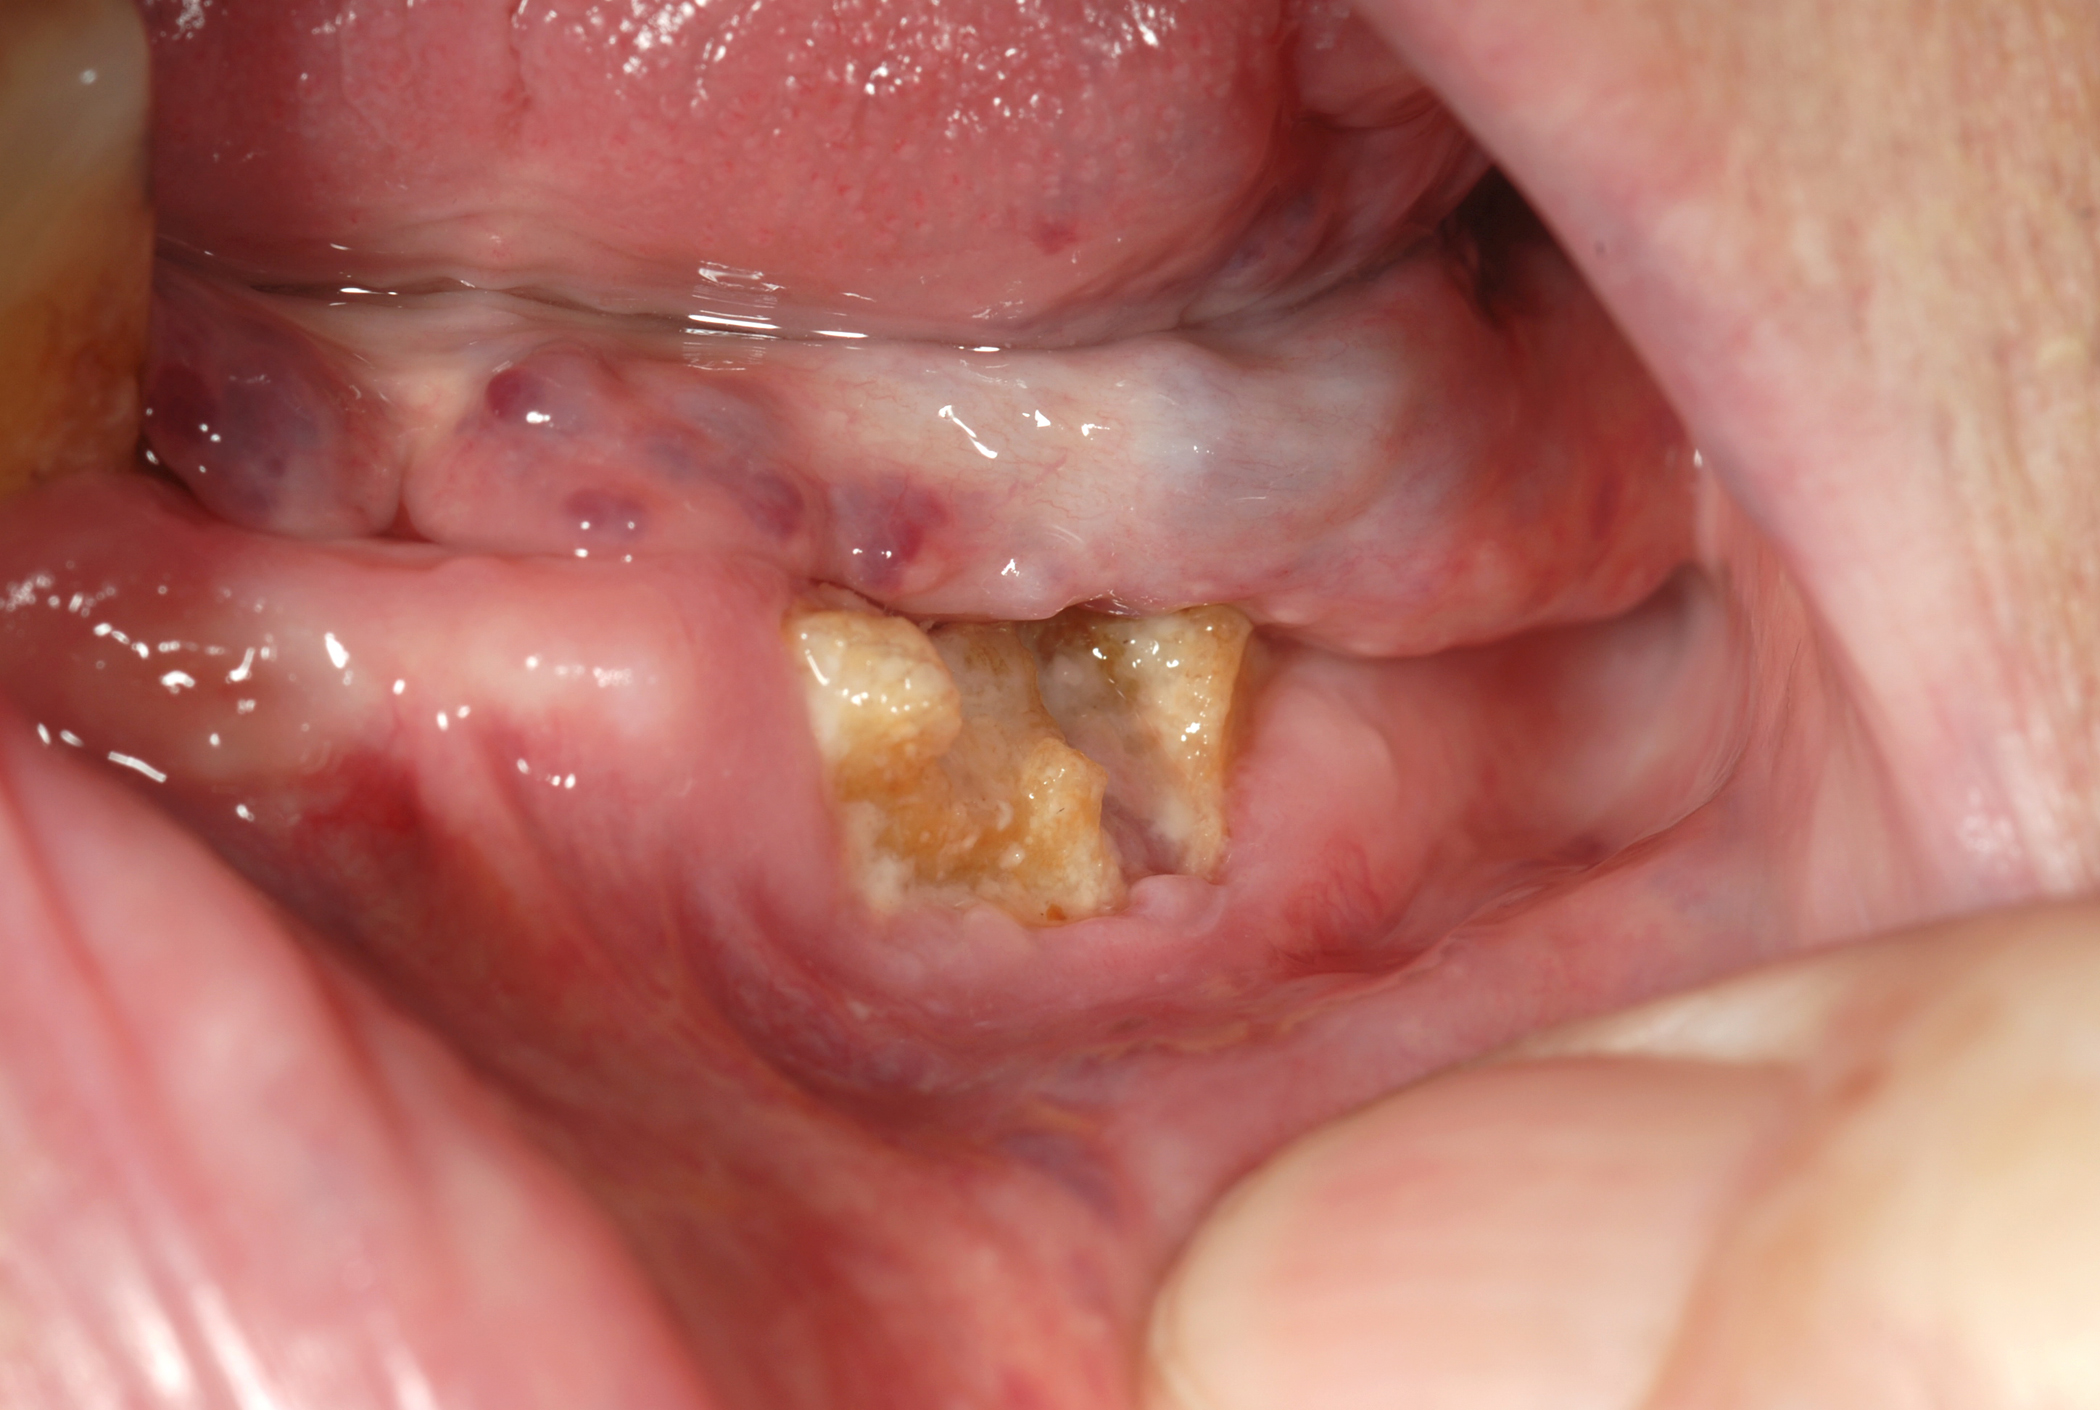

Figure 1, Figure 2 and Figure 3 show examples of different ORN conditions.

Figure 4 and Figure 5 show examples of MRONJ of the maxilla and mandible, respectively.